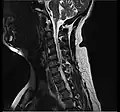

- Magnetic resonance imaging is the gold standard study for confirming a suspected LDH. With a diagnostic accuracy of 97%, it is the most sensitive study to visualize a herniated disc due to its significant ability in soft tissue visualization. MRI also has higher inter-observer reliability than other imaging modalities. It suggests disc herniation when it shows an increased T2-weighted signal at the posterior 10% of the disc. Degenerative disc diseases have shown a correlation with Modic type 1 changes. When evaluating for postoperative lumbar radiculopathies, the recommendation is that the MRI is performed with contrast unless otherwise contraindicated. MRI is more effective than CT in distinguishing inflammatory, malignant, or inflammatory etiologies of LDH. It is indicated relatively early in the course of evaluation (<8 weeks) when the patient presents with relative indications like significant pain, neurological motor deficits, and cauda equina syndrome. Diffusion tensor imaging is a type of MRI sequence used for detecting microstructural changes in the nerve root. It may be beneficial in understanding the changes that occur after herniated lumbar disc compresses a nerve root, and might help in differentiating the patients that need surgical intervention. In patients with a high suspicion of radiculopathy due to lumbar disc herniation, yet the MRI is equivocal or negative, nerve conduction studies are indicated.[44] T2-weighted images allow for clear visualization of protruded disc material in the spinal canal.

-

MRI scan of cervical disc herniation between C5 and C6 vertebrae -

MRI scan of cervical disc herniation between C6 and C7 vertebrae -

MRI scan of large herniation (on the right) of the disc between L4 and L5 vertebrae -

A rather severe herniation of the L4–L5 disc -

Example of a herniated disc at L5–S1 in the lumbar spine